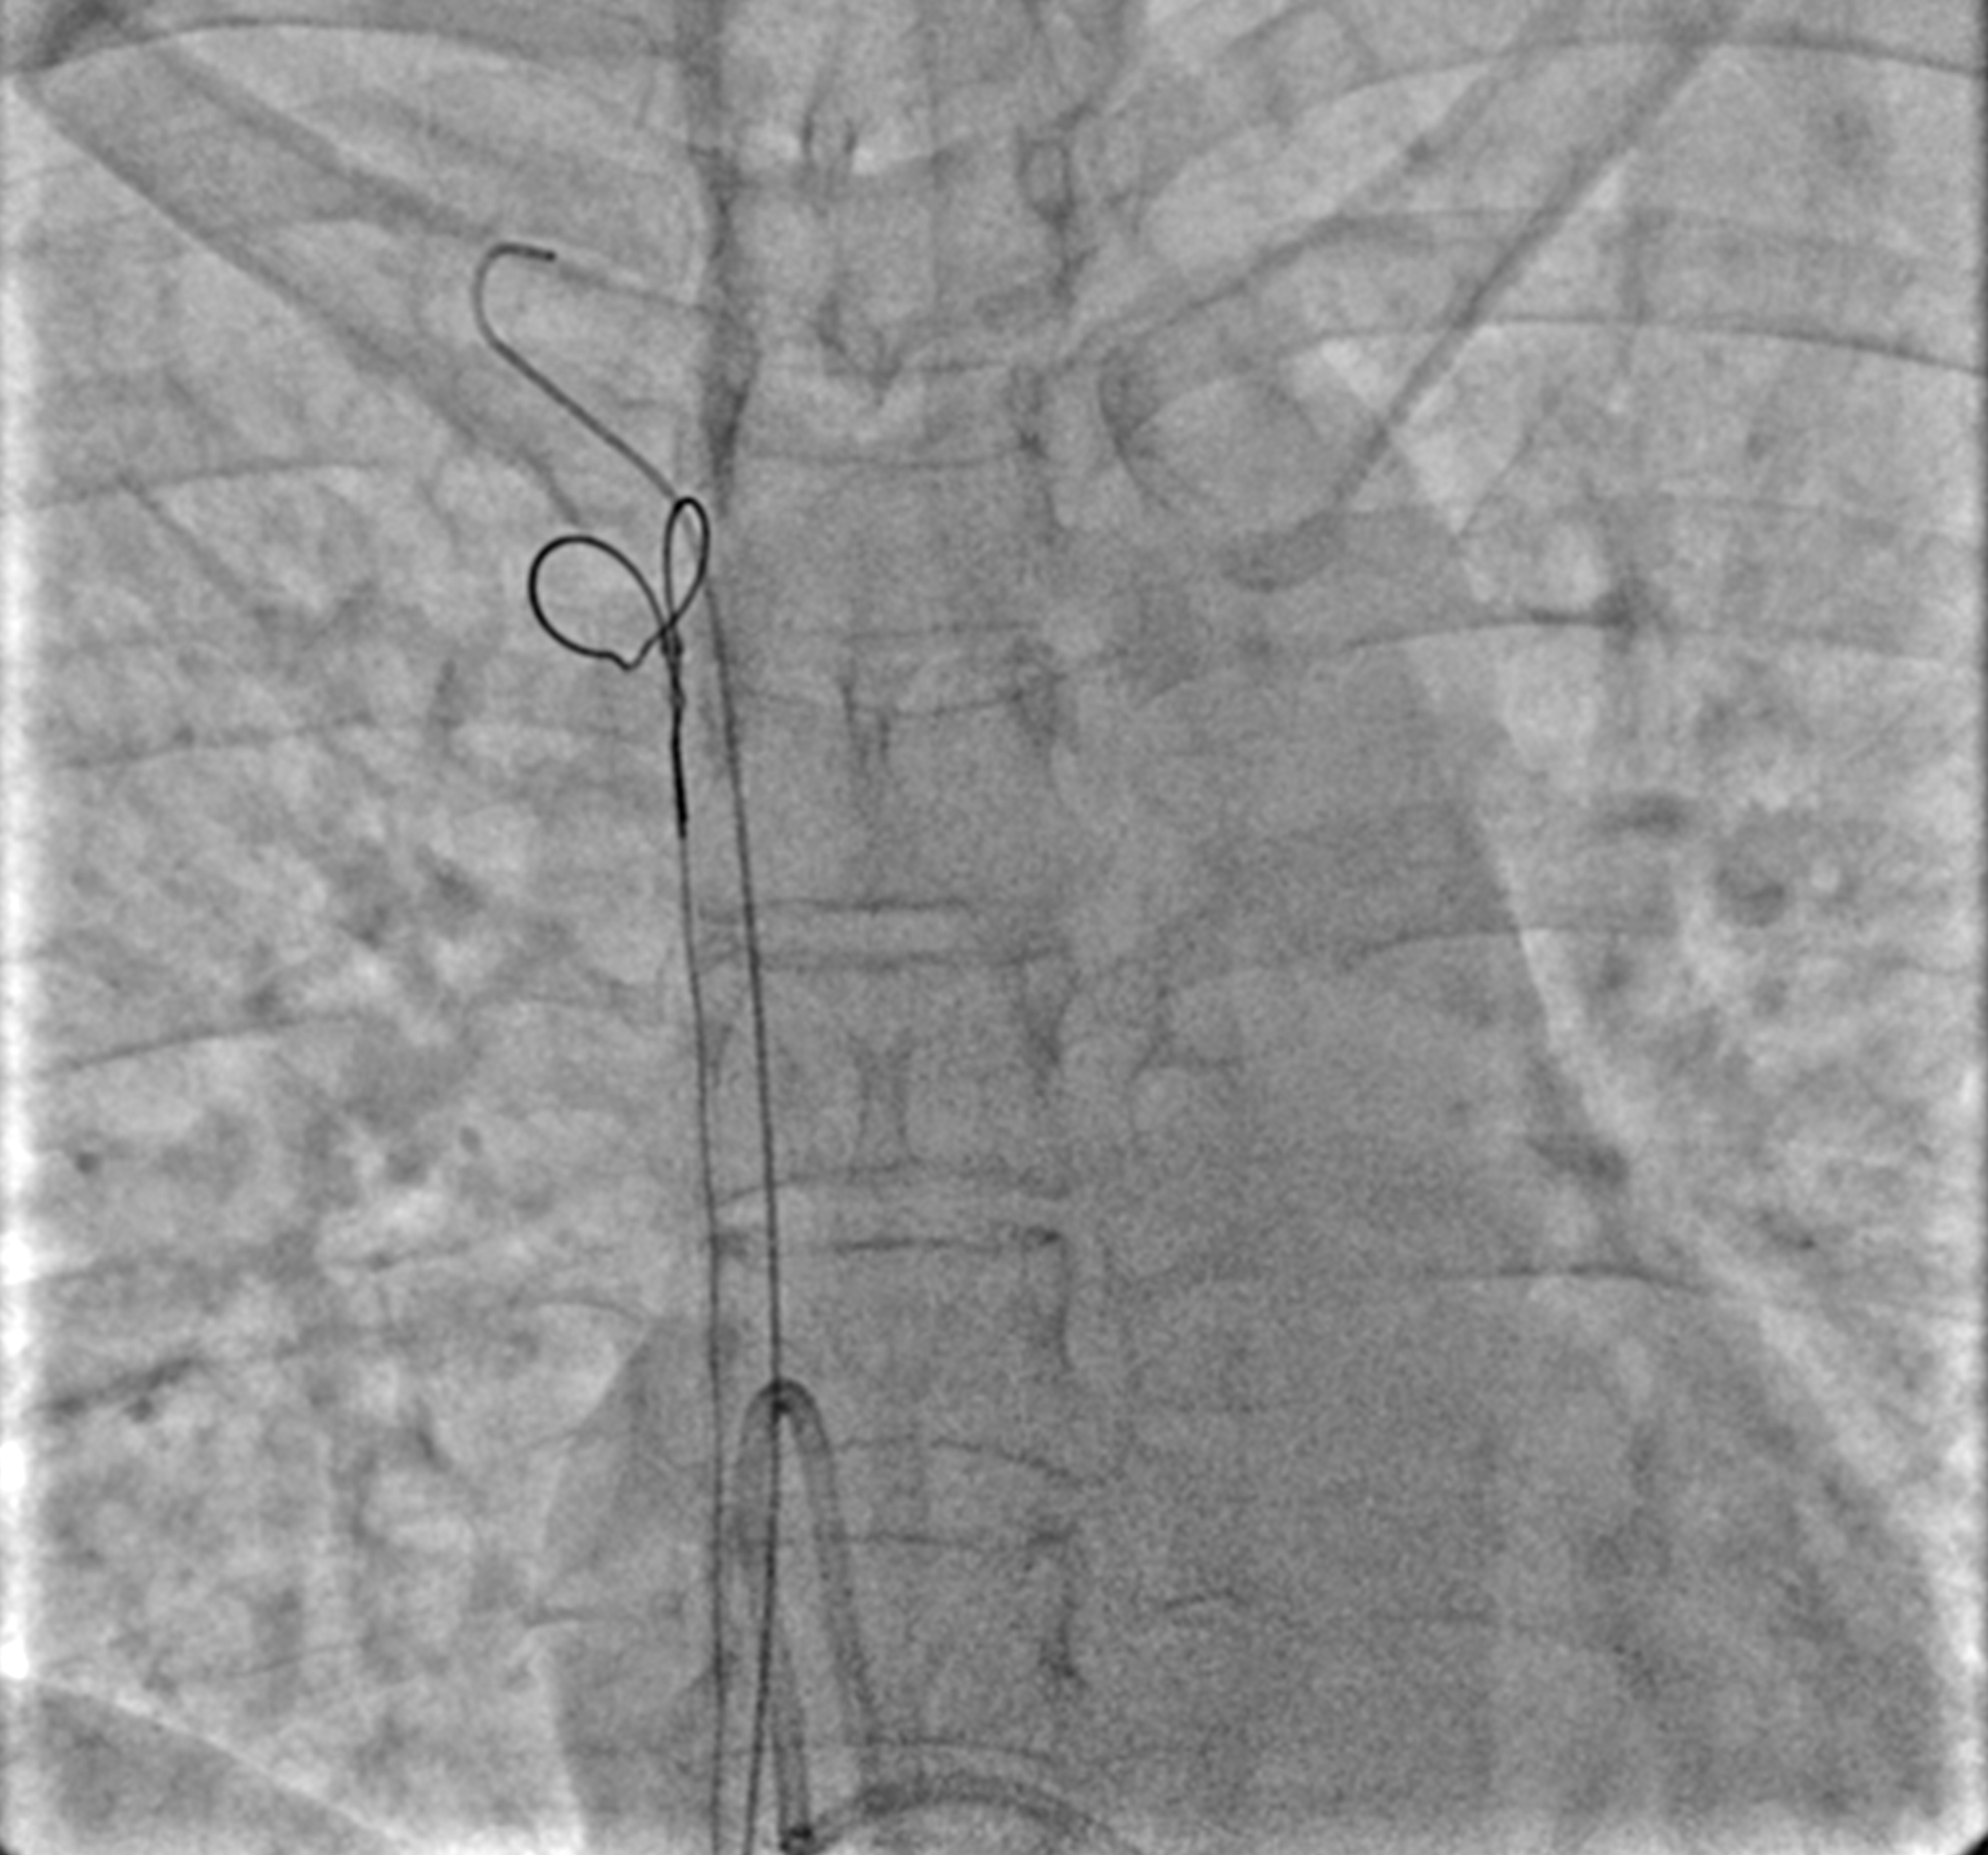

Fluoroscopic image showing the dislodged catheter segment after Dislodged Catheter Meaning This technology shuts off medication flow and preserves the catheter, while also allowing both the catheter and tubing to be protected in an aseptic manner. The key to preventing iv dislodgement, one group says,. A catheter occlusion occurs when a blockage prevents caregivers from flushing the central line or aspirating blood. In a cognitively impaired resident with a catheter suprapubic. Dislodged Catheter Meaning.

Showing the dislodged chemo port catheter looped in RA with tips in RV Dislodged Catheter Meaning When clinicians place intravenous catheters, they secure them to the catheter insertion site with one of several methods. Sometimes patients inadvertently dislodge or pull out central venous catheters; Dislodgment can cause a catheter to back out, spilling the iv fluids around the iv site instead of in the vein. This technology shuts off medication flow and preserves the catheter, while. Dislodged Catheter Meaning.

Fluoroscopic image showing the dislodged catheter segment after Dislodged Catheter Meaning Sometimes patients inadvertently dislodge or pull out central venous catheters; This technology shuts off medication flow and preserves the catheter, while also allowing both the catheter and tubing to be protected in an aseptic manner. When clinicians place intravenous catheters, they secure them to the catheter insertion site with one of several methods. A catheter occlusion occurs when a blockage. Dislodged Catheter Meaning.

Fluoroscopic image showing the dislodged catheter segment after Dislodged Catheter Meaning The key to preventing iv dislodgement, one group says,. Sometimes patients inadvertently dislodge or pull out central venous catheters; A catheter occlusion occurs when a blockage prevents caregivers from flushing the central line or aspirating blood. This technology shuts off medication flow and preserves the catheter, while also allowing both the catheter and tubing to be protected in an aseptic. Dislodged Catheter Meaning.